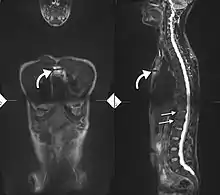

If these criteria still do not give a compelling diagnosis magnetic resonance imaging (MRI) may be useful.[21][23] MRI can show inflammation of the sacroiliac joint.

T1-weighted MRI with fat suppression after administration of gadolinium contrast showing sacroiliitis in a person with ankylosing spondylitis